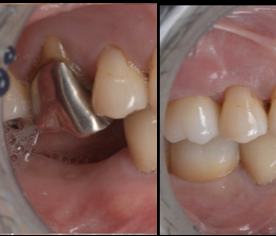

医院ブログ2025.11.09

【池袋】この歯残せる?シリーズ 抜歯と言われた...